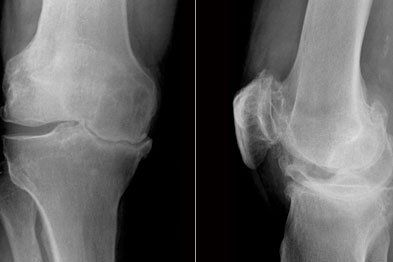

Diagnosis

A detailed subjective history in an attempt to understand the mechanism of your injury will provide a significant clue for a potential MCL/LCL injury.

During a physical examination. other potential diagnoses are excluded. A force is then applied in the direction of force described in the mechanism of injury with the knee bent initially to assess the integrity of the ligament. The knee may also be tested fully extended to assess severity. Also on palpation there is a localised tenderness and there may be some heat / swelling changes around that area.